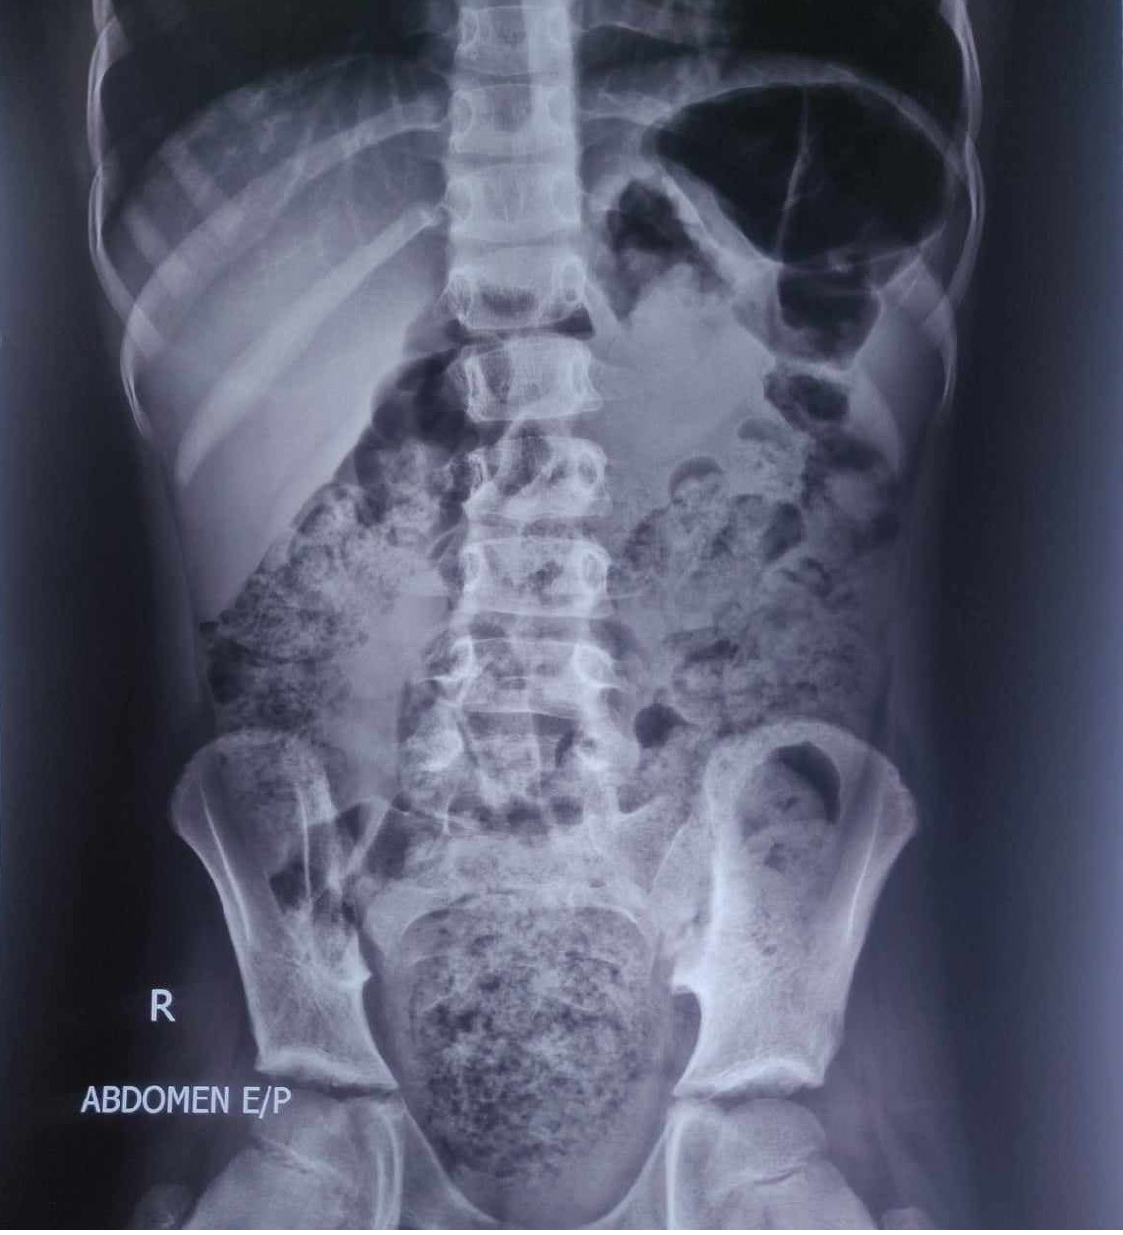

A total of 404 children were included in this study with mean age of 76.50 ± 36.62 months and male-female ratio of 1.67:1. All the children were on family food, and no gross feeding mismanagement was found. Sanitation and hygiene practices were good. Around 85% (343) of patients presented with several investigations like CBC, SGPT, serum creatinine, USG of the whole abdomen (80% of cases several times), amylase, lipase, etc., but only 3% (12) did a plain X-ray abdomen. During enrollment in this study, no definite secondary pathology or co-morbidity was present. The most common presenting complaint was abdominal pain (66%, 266), followed by anorexia (49%, 199), vomiting (24%, 97), nausea (17%, 69), frequent defecation with small volume stool (17%, 67), altered bowel habit (16%, 63), failure to thrive (14%, 57), recurrent helminthiasis (12%, 50), mucoid stool with straining during defecation (3%, 12), and encopresis (3%, 12). About 9% (36) of children had abdominal distention due to excessive colonic gas. Interestingly, 2.5% (10) children presented with persistent diarrhea, and 2% (8) children presented with repeated history of diarrhea. Palpable fecal mass was present in 7.92% (32) children, among them two patient was diagnosed as pelvic mass (both clinically and by USG), latter CT abdomen shows huge fecal impaction at rectum (Figure 2). Urinary complaints were also common, like increased frequency of micturition (7.5%, 30) and nocturnal enuresis (6%, 24). Other catchy points: 3% (13) children presented with unexplained excessive crying at night, which we diagnosed as pinworm infection with the presence of a worm on the rectum (Table 1). All the symptoms were significantly improved at the end of treatment and sustained during follow-up (Table 2). But few patients failed to improve after 2 months of treatment, and they were with chronic kidney disease (CKD) with obstructive uropathy (1, anorexia, nausea and occasional vomiting not improved), CKD due to tethered cord syndrome (1, urinary symptoms not improved), CKD (1, anorexia, nausea and occasional vomiting not improved), celiac disease (1, abdominal pain not improved), hypothyroidism (1, patient was overweight and abdominal distension not improved), intestinal tuberculosis (1, abdominal pain not improved), sacral meningocele (1, abdominal distension not improved), and lost to follow-up (4 cases).

Figure 2

Figure 2 Computed tomography scan of abdomen showing fecal mass at pelvis.